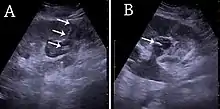

- Figure 26. Acute pyelonephritis with increased cortical echogenicity and blurred delineation of the upper pole.[1]

- Figure 27. Postoperative renal failure with increased cortical echogenicity and kidney size. Biopsy showed acute tubular necrosis.[1]

- Figure 28. Renal trauma with laceration of the lower pole and subcapsular fluid collection below the kidney.[1]